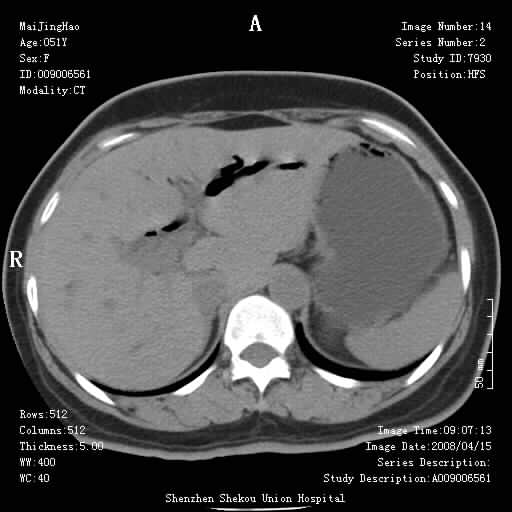

以下是引用余辉在2008-4-26 8:55:00的发言:[br]患者有结石史,此次腹痛4小时,胆总管全程扩张,应有胆总管末端梗阻,此次仍考虑胆结石症,积气不外两种原因,一种是结石下移时肠道内气体逸入,其次为产气菌感染。(倒数第三幅图像于扩张之胆总管末端似可见稍高密度影,考虑为结石影)

以下是引用yangyudong333在2008-4-26 6:17:00的发言:[br]1胆系感染,可能为金葡菌感染,2考虑有化脓性胆管炎致胆总管扩张,3胰头部增大,建议做增强

以下是引用听蝉观竹在2008-4-26 11:41:00的发言:[br]胆道手术分两种情况:[br]1、如果仅仅做胆囊切除手术,肝内胆管不会积气,只会出现胆总管代偿扩张,因为奥迪氏括约肌依然功能正常胆道与外界并不相通;[br][br]2、胆囊切除+胆总管空肠吻合手术(即roux-y式),则肝内胆管会出现积气,只是因为胆管与小肠相通,气体来源于小肠。这是临床十分常见的手术。[br][br]这个病例应该是胆囊切除+胆总管空肠吻合手术,是正常手术后表现,并不是胆道感染的表现。

以下是引用宇宙ct在2008-4-26 10:43:00的发言:[br][br] 胆囊切除术后胆管常因代偿而出现扩张,肝内胆管也经常会出现积气征象;胰头强化后再诊断。 [br] [br]

以下是引用听蝉观竹在2008-4-27 10:10:00的发言:[br]关于胰头大小问题有几种测量方法和正常值:[br][br]1、直量法:横径<4cm;[br]2、胰头横径与相邻层面椎体横径的比值为二分之一,超过椎体横径就提示胰头增大;[br]3、正常组成年人肠系膜上动、静脉水平夹角正常值范围为4.9°~34.7°大于35°提示胰头增大。[br][br]上述方法只是一种具体的判断,是“量”的评估,更重要的是“质”的评估:一是观察边缘是否光滑,有无局部隆起,有无分叶;二是观察密度(增强,尤其在动脉期和门脉期)是否均匀。[br][br]所以对于胰头是否有异常不仅仅是是目测可以解决问题的,不要轻易就说“胰头增大”。还有一个问题就是测量胰头应该在增强ct上进行,这样可以避免将血管测量进去。[br][br]为什么啰嗦讲怎么多,因为我们实际工作中同样存在影像科医生和临床医生动不动就说胰头增大,说是胰头癌。大家看看是不是这种情况?[br][br] 我个人观点-----本病例的胰头不增大。[br][br][本贴已被 听蝉观竹 于 2008-4-27 10:12:41 修改过]